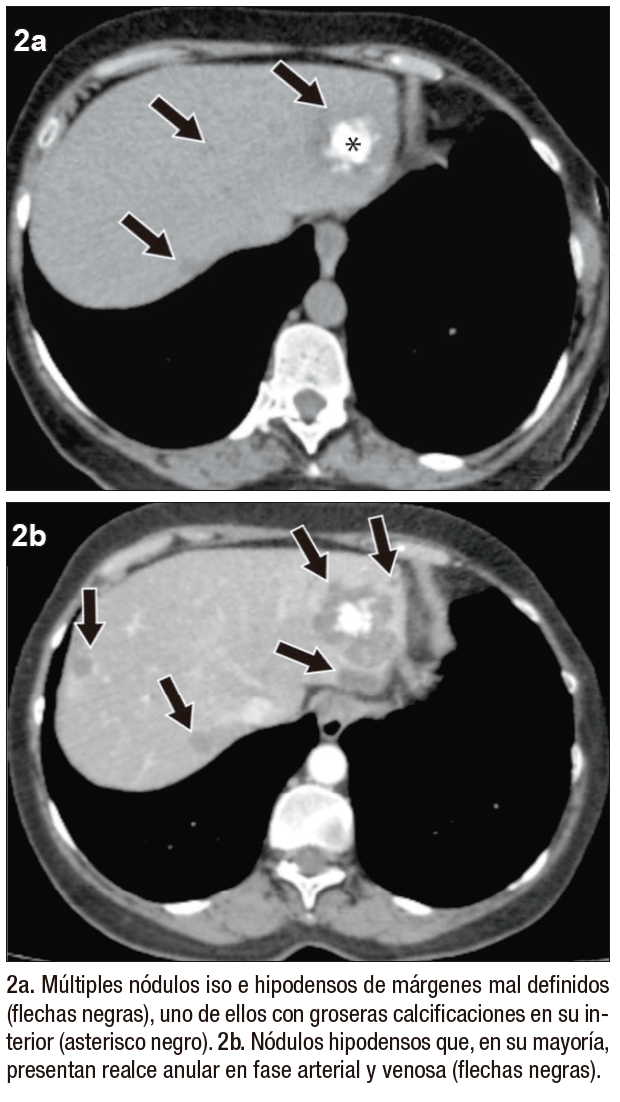

Posteriormente, se realiza una ecografía abdominal en la que se muestran innumerables nódulos hipoecogénicos, de márgenes parcialmente circunscritos, con calcificaciones en su interior, algunos causantes de retracción capsular, sin evidencia de flujo vascular con Doppler color (Figura 1). Tras estos hallazgos, se continúa la valoración mediante TCMD (Tomografía Computada Multi detector) con contraste endovenoso, donde se observan, en consonancia con la ecografía, numerosos nódulos isodensos e hipodensos, con realce en anillo en fases arterial y venosa, distribuidos en ambos lóbulos hepáticos.

En el lóbulo izquierdo se destaca un nódulo dominante, acompañado de groseras calcificaciones internas, que mide 48x42x39 mm (Figura 2).

Figura 2. TCMD hepática en corte axial, sin contraste (2a) y con contraste endovenoso (2b-d). Fase arterial (b)

Figura 2. 2c y 2d) Fase venosa